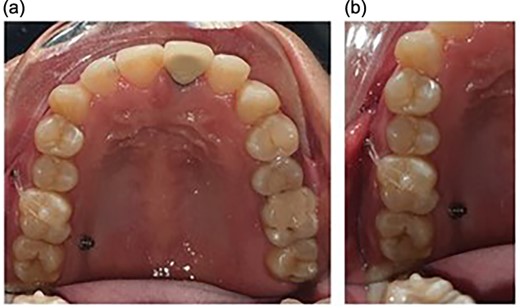

Following the placement of miniscrews, immediate loading was done with 100 g of intrusive force using a short power chain. The power chain was passed and engaged onto the composite button to ensure the forces are directed occlusally and there is no slippage. The patient was followed up at 4-week intervals and the power chain was replaced with one link, which was reduced at each appointment. After the first month, the dental implant was placed to replace the mandibular first molar. After 5 months of intrusion, the desired occlusal clearance was achieved and the upper and lower impressions were recorded (Fig. 2). For retention in the upper arch, the patient was given a clear vacuum retainer, while the crown was placed on the implant to prevent any relapse and to achieve good occlusion.

The intrusion process with placement of the prosthetic crown at the completion stage.